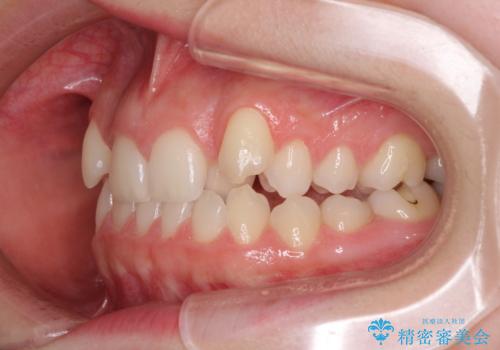

- 前歯のデコボコと八重歯を気にして来院された患者様です。

目立たない装置を希望されたので、上顎が裏側装置のハーフリンガルを選択し、左右上顎小臼歯1本ずつを抜歯して、矯正治療を行うこととしました。

治療期間の目安は2年半~3年間でしたが、予定通り治療が進み、2年半弱で終えることができました。

歯列はきれいに整い、治療期間も予定通りであり、患者様には大変満足していただきました。